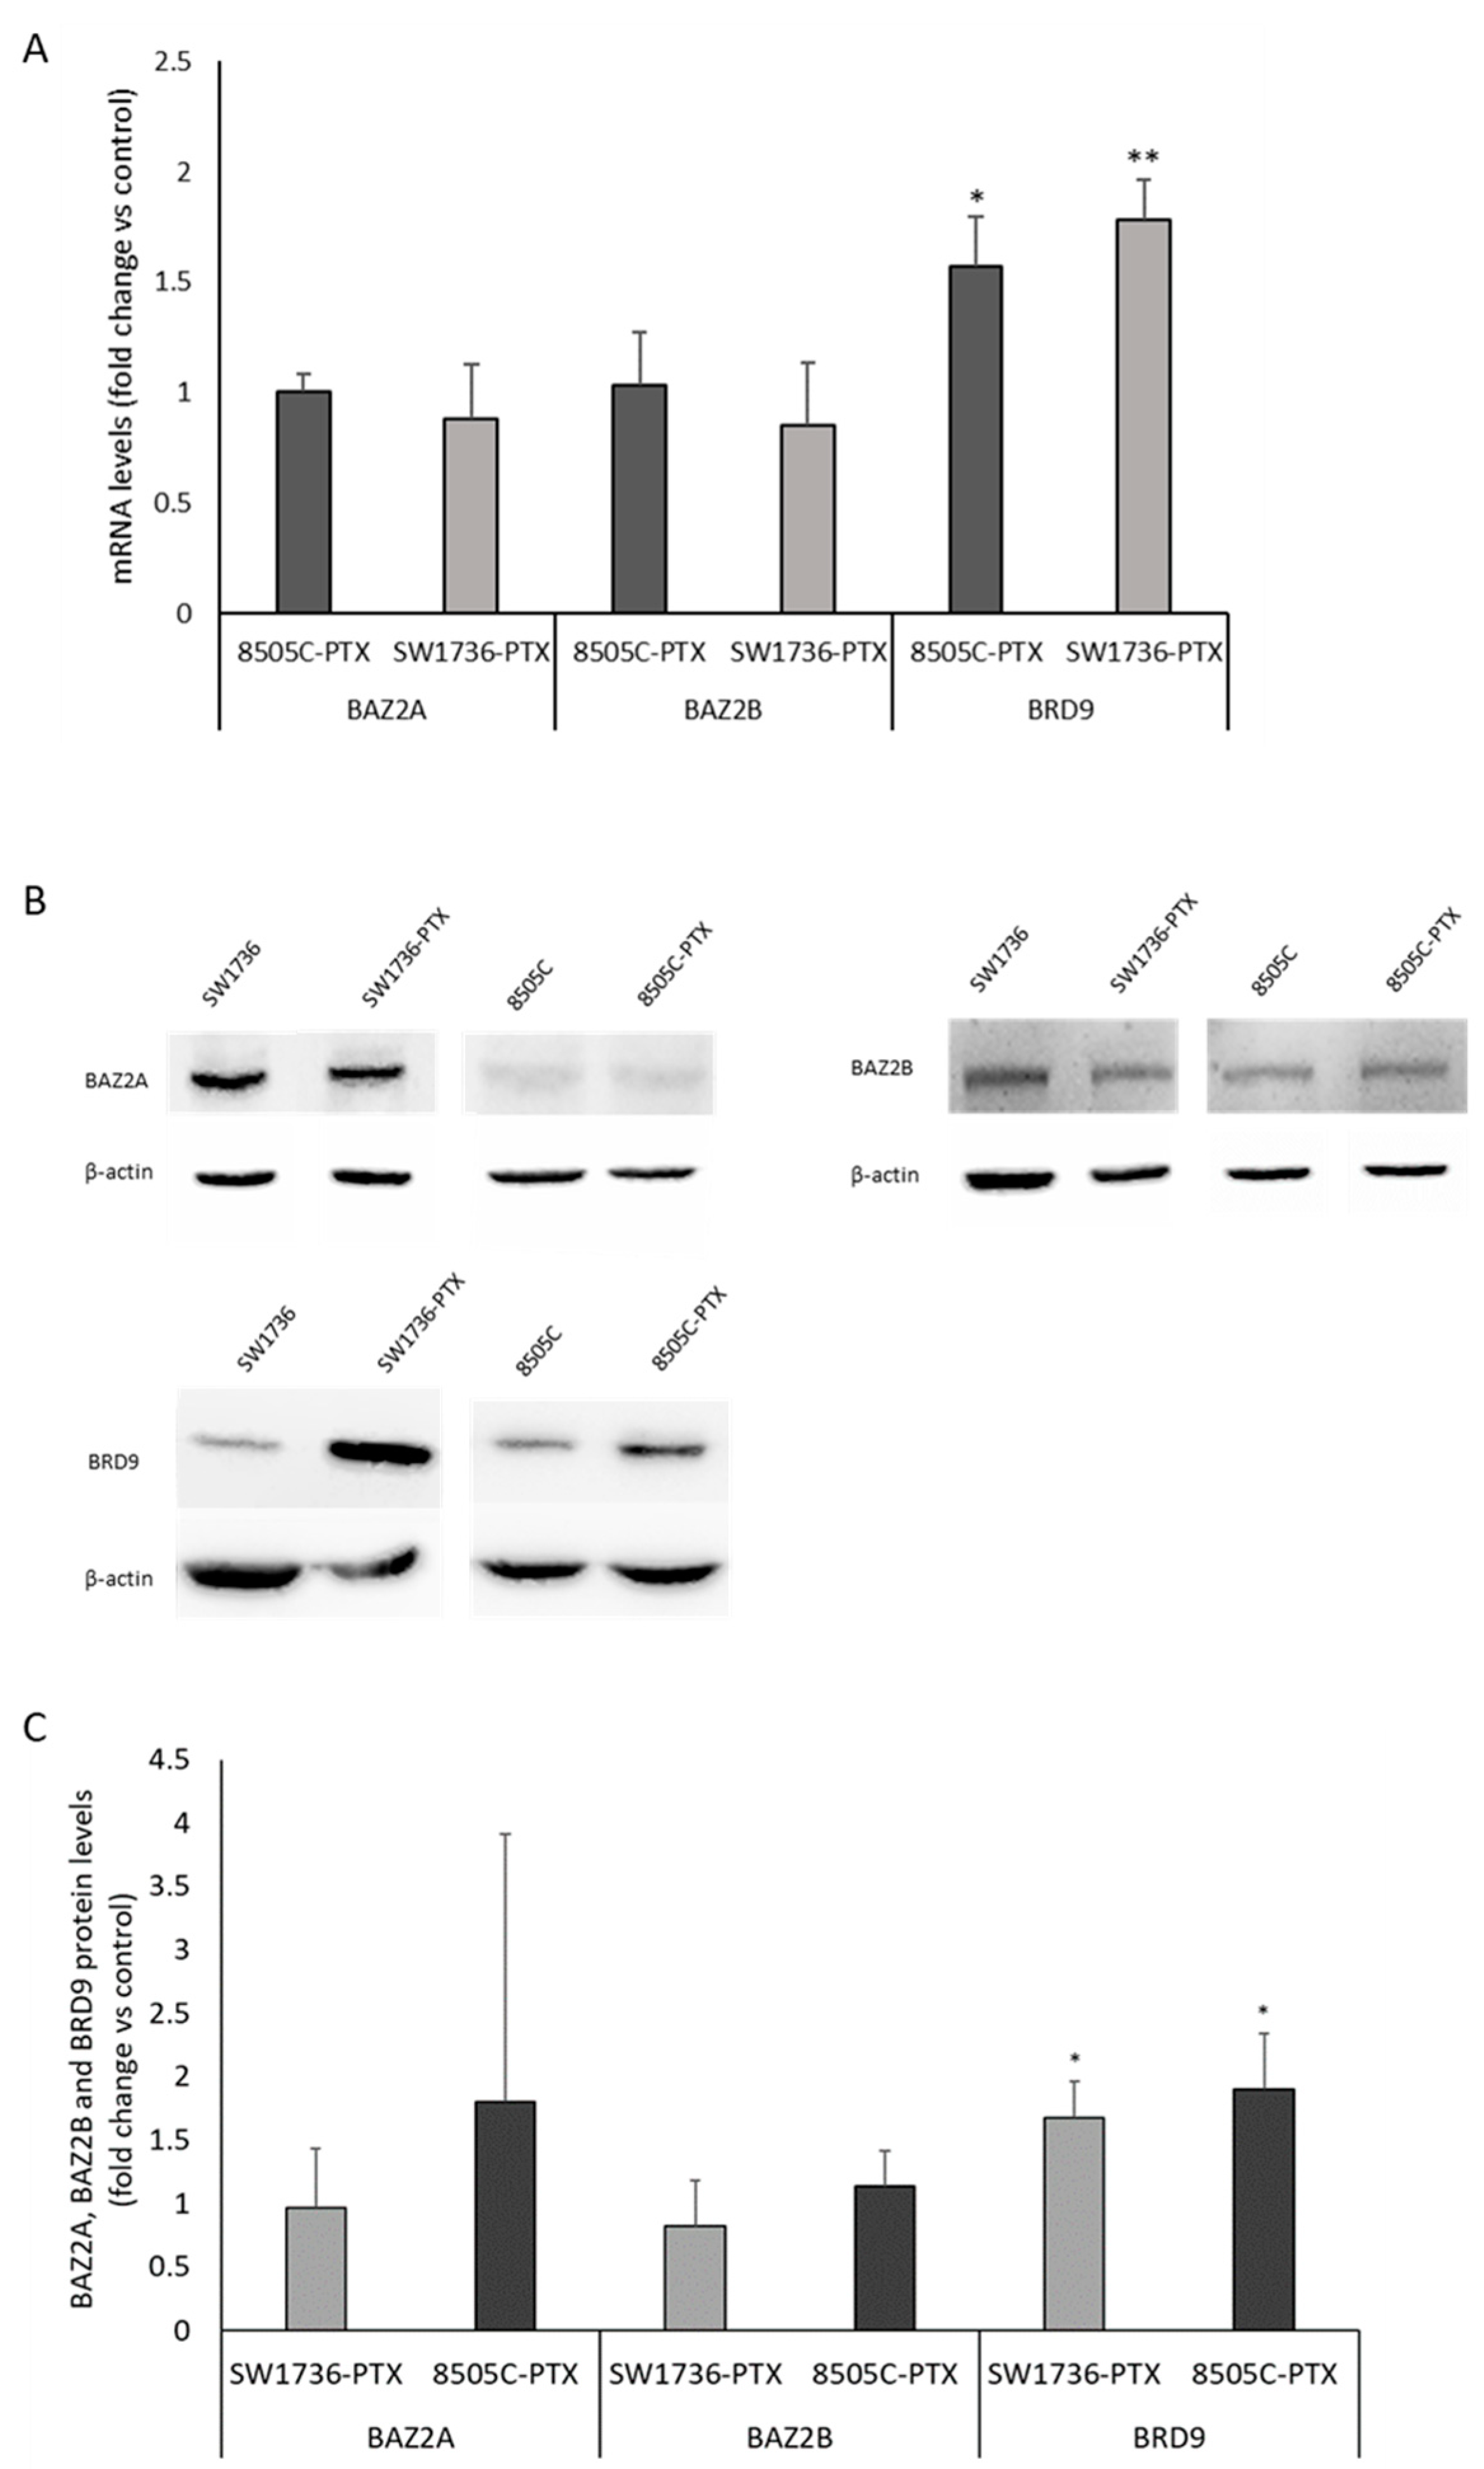

IJMS Free Full Text GSK2801 Reverses Paclitaxel Resistance In

IJMS Free Full Text GSK2801 Reverses Paclitaxel Resistance In